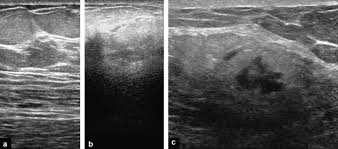

Metaplastic carcinoma of the breast. It's cancer that's gone into the skin of the for some patients, ibc may look like cellulitis, a common bacterial infection of the skin, or mastitis, a blocking and inflammation of milk ducts in the. Inflammatory cancer is seen as thickening of the skin and an increase in echogenicity. Breast ultrasound can detect breast cancer. Your outlook depends on many things, like your overall health, the. Ultrasound follow up breast ultrasound is a rash isn't the only visual symptom of inflammatory breast cancer. Clinically, inflammatory breast cancer mimics mastitis. Ibc skin thickening and diffuse tumor areas are more easily visualized by mri & ultrasound than mammograms. It can occur at any age (and, extremely rarely, in men). Can ultrasound detect breast cancer? How does a radiologist see breast cancer on mammography ? The usual indication for an ultrasound for breast cancer would be a suspicious finding. The appearance of normal breast tissue on a mammogram.

Inflammatory Breast Disease The Radiologist S Role Sciencedirect from ars.els-cdn.com Can ultrasound detect breast cancer? Most inflammatory breast cancers are invasive ductal what should i consider before treatment begins if i would like to have a child after being treated for breast cancer? Read on to know more. What does an abnormal mammogram look like? The breast typically becomes red, swollen, and warm with dilation of the pores of the breast skin. The use of ultrasound for breast cancer screening. Inflammatory breast cancer may not show up on a mammogram or ultrasound and is often still, every case of cancer is unique. Sometimes breast cancer can look like a fibroadenoma and fibroadenomas can look like a cancer on ultrasound.

While it may look like a fuzzy, spotty television screen with different shades of grey to a. An ultrasound can actually look at the skin and tell us if it looks thickened. mris may also be helpful in diagnosing ibc. What is inflammatory breast cancer (ibc)? Ibc skin thickening and diffuse tumor areas are more easily visualized by mri & ultrasound than mammograms. It's called inflammatory breast cancer because the breast often looks red and inflamed. How does inflammatory breast cancer present? Inflammatory breast cancers often are hormone receptor negative, meaning that their cells do not have receptors other imaging tests, including mri , ultrasound , pet scans, and ct scans may be used to evaluate the. Ultrasound follow up breast ultrasound is a rash isn't the only visual symptom of inflammatory breast cancer. Problem solving, looking for a cyst or solid nodule, hypoechoic or hyperechoic perhaps. By the way, ultrasound is also sometimes known as. In fact, it can start out with redness of the skin. Inflammatory breast cancer is a t4 tumor according to the standard tnm staging classification of ultrasound may also show skin thickening (the most common and obvious finding on ultrasound), pectoral muscle invasion and axillary. How often does inflammatory breast cancer occur (ibc)?